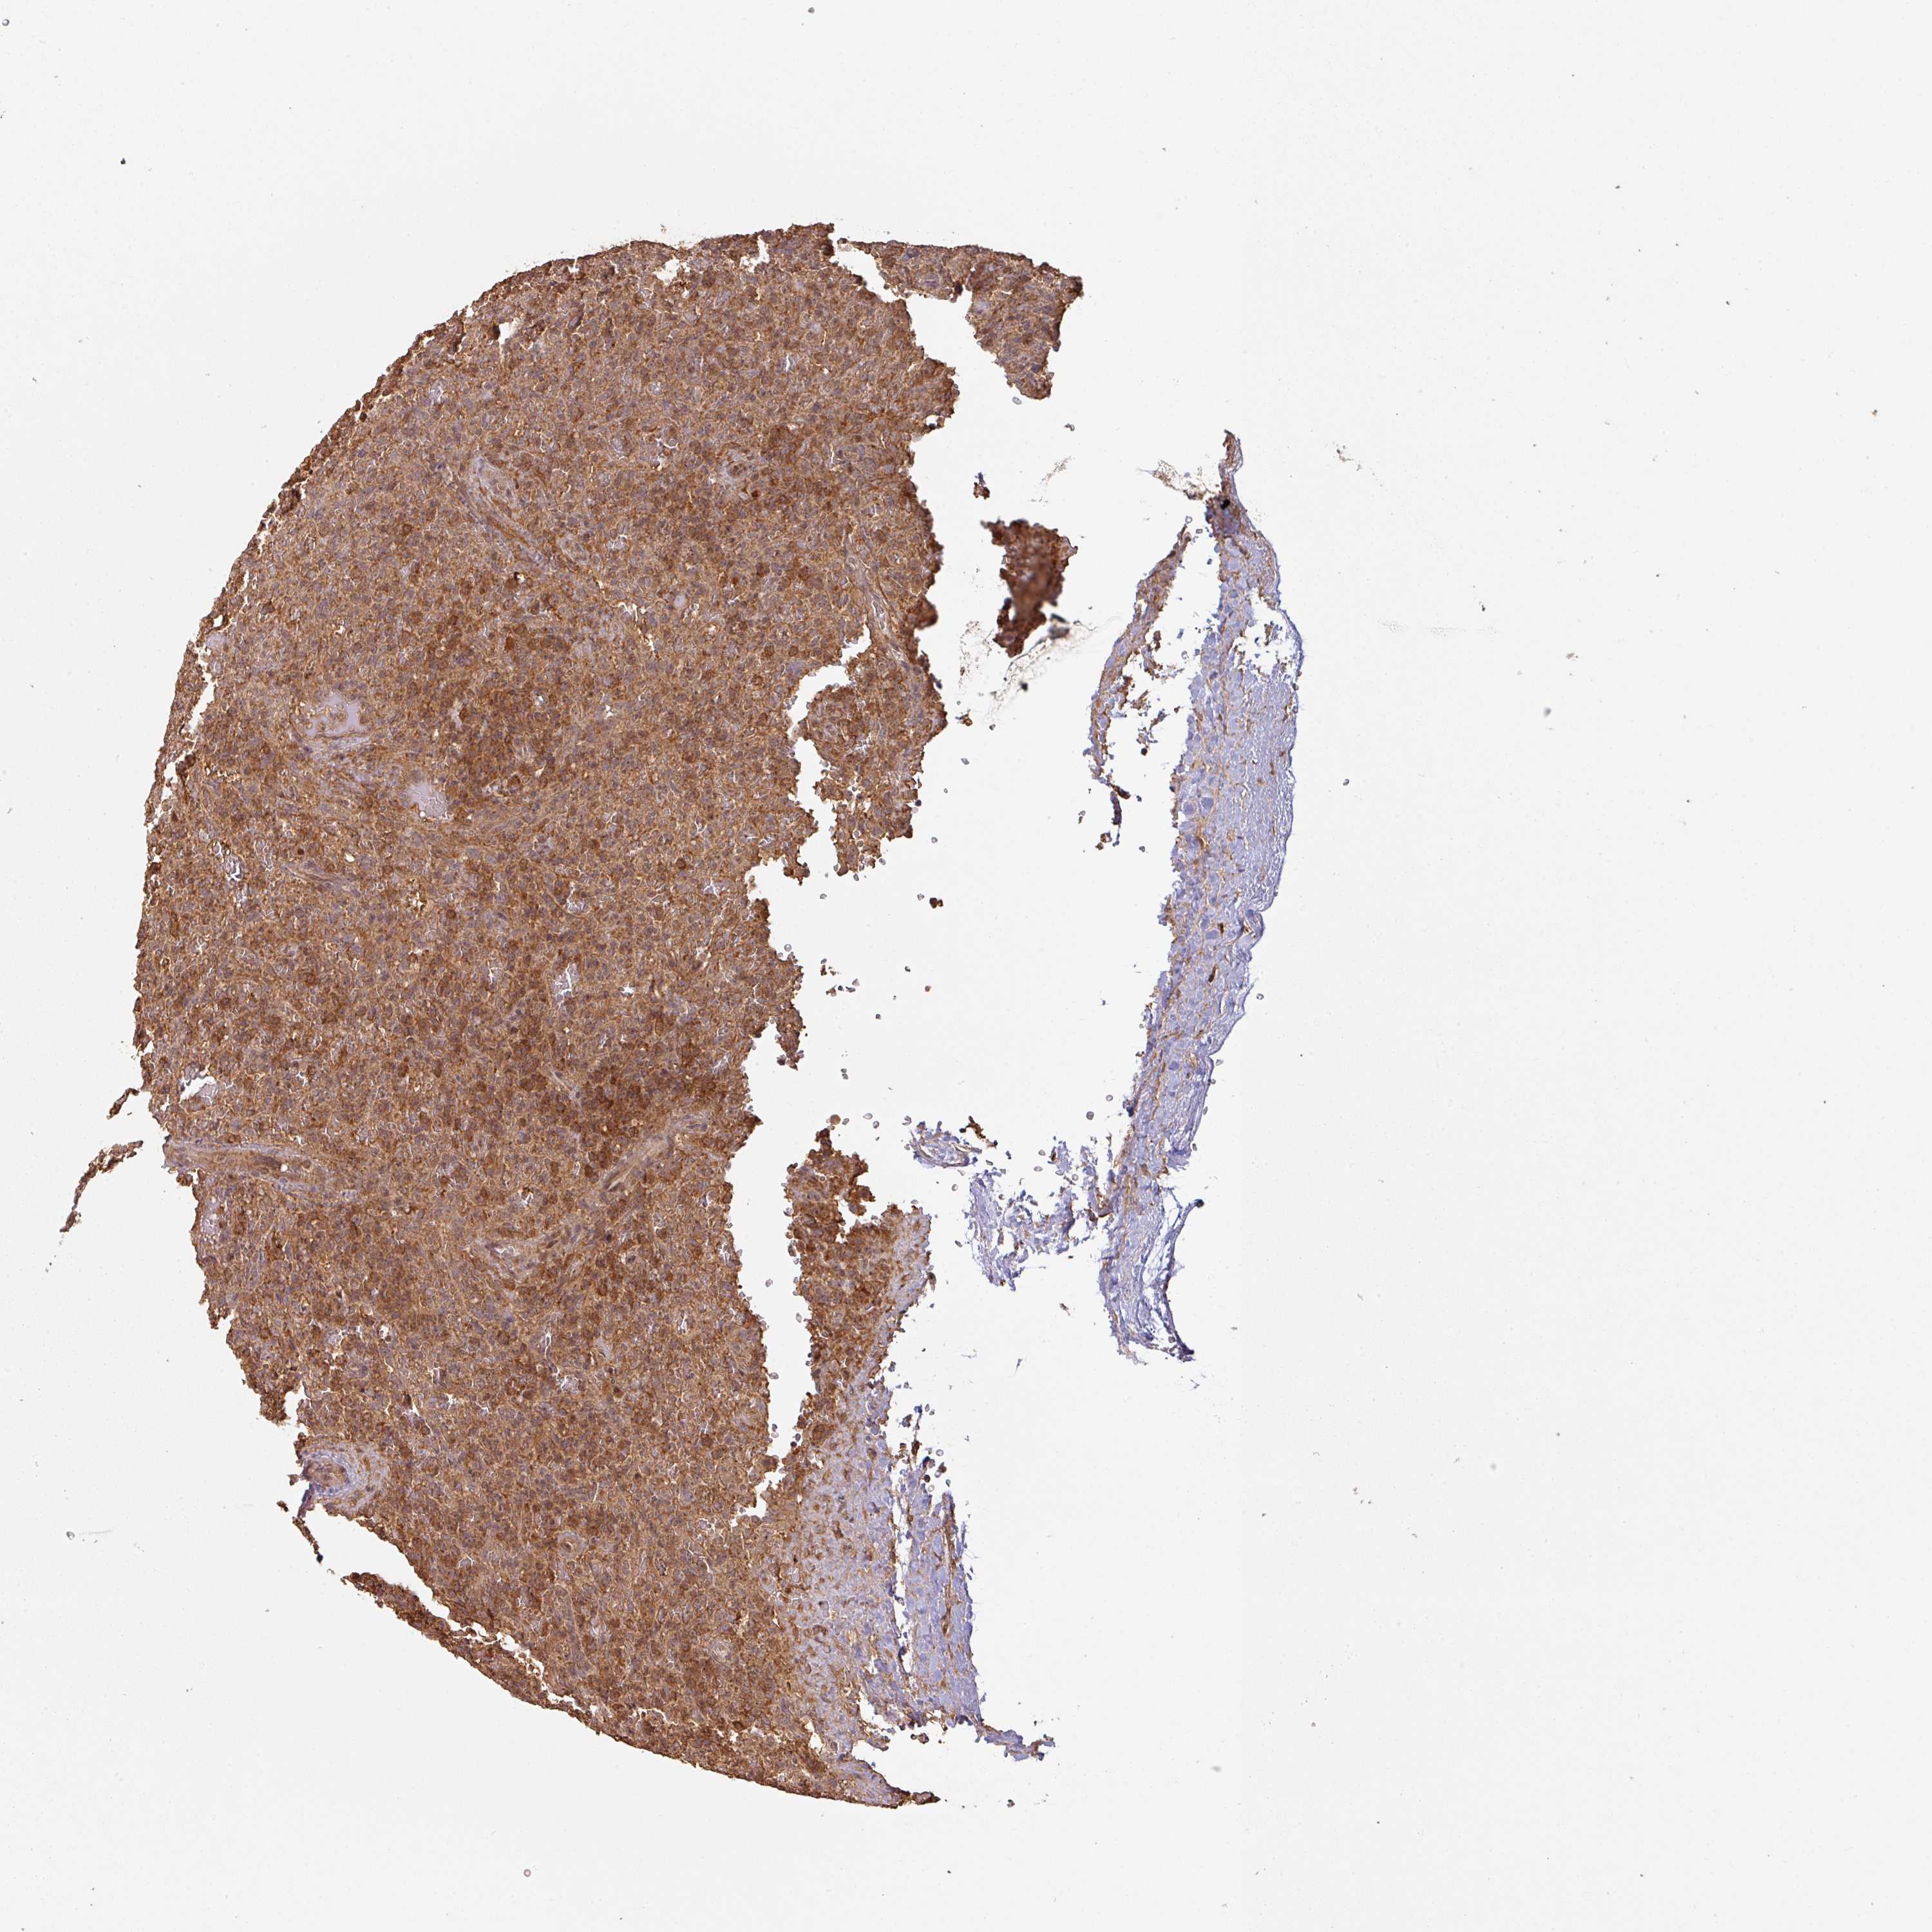

LYMPHOMA - Protein expressioni

A mouse-over function shows sample information and annotation data. Click on an image to view it in a full screen mode. Samples can be filtered based on level of antibody staining by selecting one or several of the following categories: high, medium, low and not detected. The assay and annotation is described here.

Antibody staining in the annotated cell types in the current human tissue is reported as not detected, low, medium, or high, based on conventional immunohistochemistry profiling in selected tissues. This score is based on the combination of the staining intensity and fraction of stained cells.

Each image is clickable and will lead to virtual microscopy that enables deeper exploration of all samples and also displays staining intensity scores, fraction scores and subcellular localization as well as patient and tissue information for each sample.

Antibody HPA043161

Antibody HPA046692

Staining

High

Medium

Low

Not detected

Intensity

Strong

Moderate

Weak

Negative

Quantity

>75%

75%-25%

<25%

None

Location

Nuclear

Cytoplasmic/membranous

Cytoplasmic/membranous,nuclear

Malignant lymphoma, non-Hodgkin's type, Low grade

Malignant lymphoma, non-Hodgkin's type, High grade

Hodgkin's disease, NOS